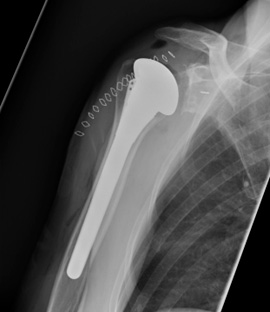

Omvendt skulderprotese

Ved den omvendte skulderprotese har man byttet om på ledhoved og ledskål. Det vil sige, at ledkuglen fæstnes på skulderbladets ledskål, og ledskålen placeres på overarmsknoglen. Denne type protese bruges i tilfælde, hvor styresenerne i skulderen er ødelagte, som for eksempel ved styresene gigt. Ved at vende protesen om, er der ikke behov for styresenerne til at løfte armen, og man kan i stedet kompensere ved at bruge skulderrundings musklen (deltoideus).

Den omvendte skulder er også førstevalget ved komplicerede skulderbrud og følger efter skulderbrud. Endelig bruges den omvendte skulder, hvis der er dårlig knoglekvalitet på ledskålen.

Røntgenbillede viser en omvendt skulderprotese

Viser en omvendt skulderprotese. Ledhovedet er nu placeret på skulderbladets ledskål. Ledskålen sidder nu forankret ned i overarmsknoglen.